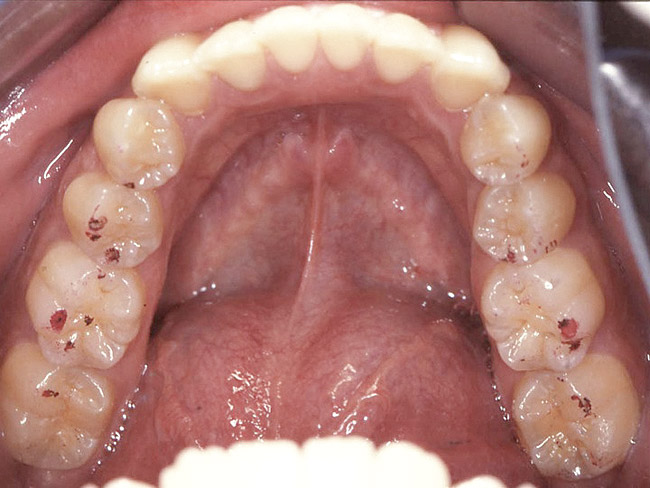

Figure 6. The patient is congenitally missing the maxillary lateral incisors and canines and all lower incisors and canines, causing concerns about esthetics. The maxillary laterals and canines and mandibular canines have been bonded with composite.

Figure 6

Loss of vertical dimension can be assessed through patient examination intraorally, extraorally, and functionally. Missing teeth and/or teeth worn from clenching or bruxing are the most common intraoral signs of a decreased VDO. Congenitally missing teeth can result in loss of vertical dimension with possible implications of compromised comfort, speech, and chewing (Figure 6 through Figure 8).